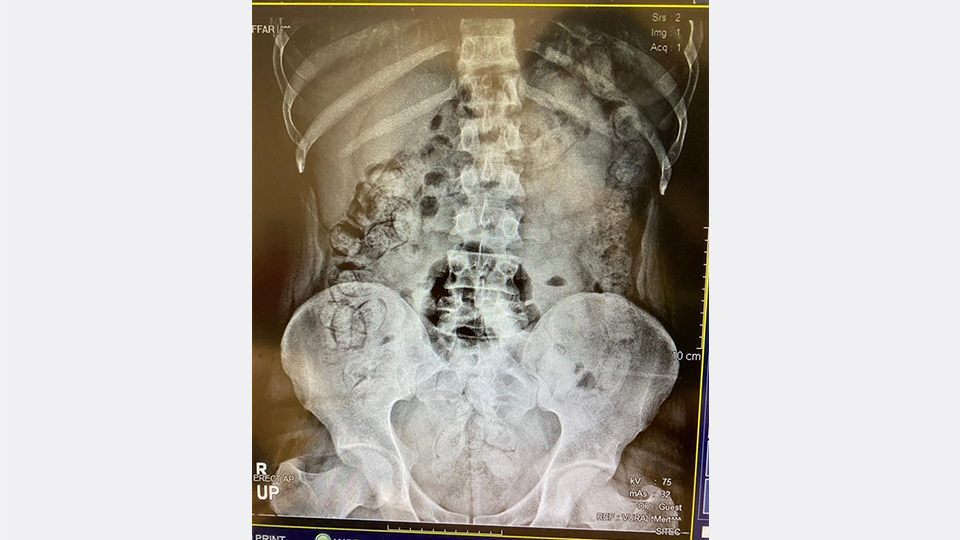

Çekilen röntgen filmlerinde şüphelilerin vücutlarında 62 kapsül eroin ve 210 kapsül afyon sakızı olduğu tespit edildi.

Röntgen çekimlerinde uyuşturucu kapsüllerinin şüphelilerin neredeyse iç organlarının her tarafına yayıldığı belirlendi.

Yapılan kontrollerde ve röntgen çekimlerinde, şüphelilerin vücutlarından 411 kapsül afyon sakızı olduğu belirlendi.

İlk operasyonda ve ikinci operasyonda yakalanan zanlıların, uyuşturucuları bugüne kadar rastlanılmayan "kolonoskopi" yöntemiyle vücutlarına yerleştirdikleri değerlendirildi.